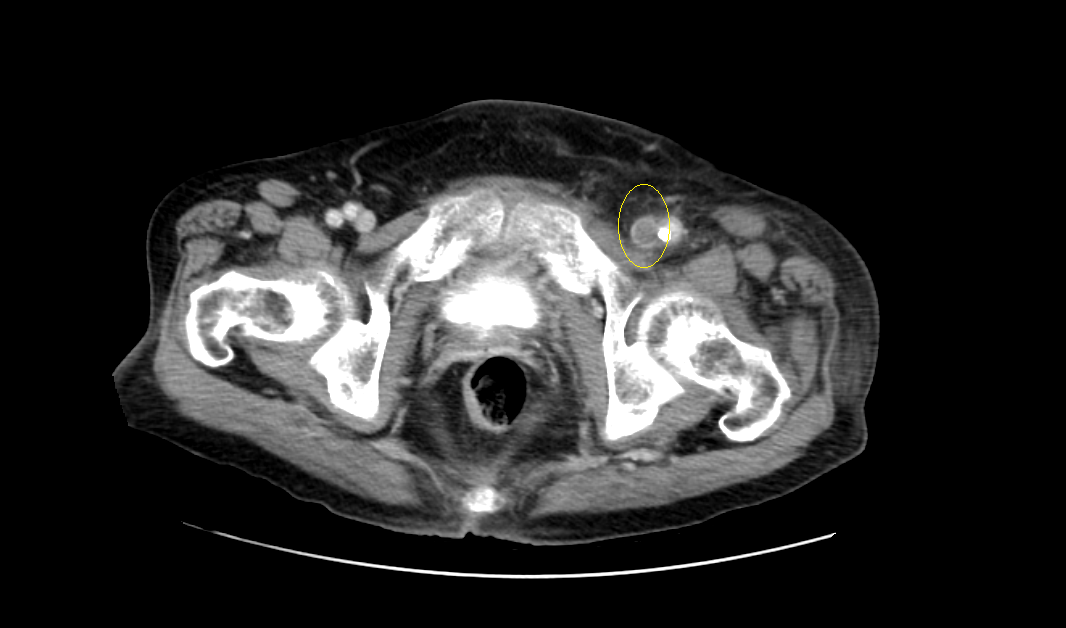

영상은 머리에 가까운 복부에서 다리 쪽으로 가는 순서로 나열하였다.

CT영상을 보면 좌측 장골정맥과 우측 장골동맥이 교차하는 지점에서부터 다리 말단 쪽으로 내려가며, 총장골정맥-외장골정맥-총대퇴정맥-표대대퇴정맥-오금정맥-경골정맥까지 혈전이 차있는 모습을 확인할 수 있었다.

Acute DVT, left CIV, EIV, IIV, CFV, SFV, popliteal and crural veins with compression of left CIV between vertebra and right CIA, c/w acute DVT with May Thurner syndrome.